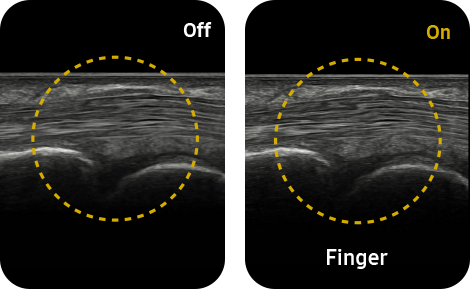

HQ-Vision™ ¹ provides clearer images by mitigating the characteristics of ultrasound images that are slightly blurred than the actual vision.

Reduce noise to improve